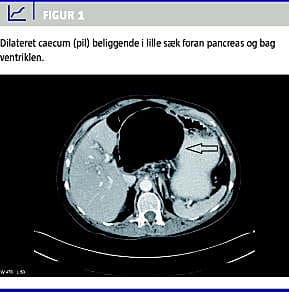

På mistanke om galdestenssmerter blev der den følgende dag foretaget ultralyd (UL)-undersøgelse af den øvre abdomen, hvor man fandt let dilateret ductus choledochus og mistanke om ileus. Patienten havde fortsat de samme smerter og havde ingen afføring haft siden indlæggelsen. UL-undersøgelsen blev suppleret med en computertomografi (CT) af abdomen, hvilket overraskende viste at, caecum var dilateret til 9 cm og beliggende foran pancreas, bag ved ventriklen ved lille sæk (Figur 1 ).

Diagnosticering af herniering til lille sæk sker bedst ved CT, som bør udføres tidligt ved ukarakteristiske øvre abdominalsmerter. Skanningen kan afsløre et luftfyldt tarmsegment mellem ventrikel og pancreas (Figur 1).